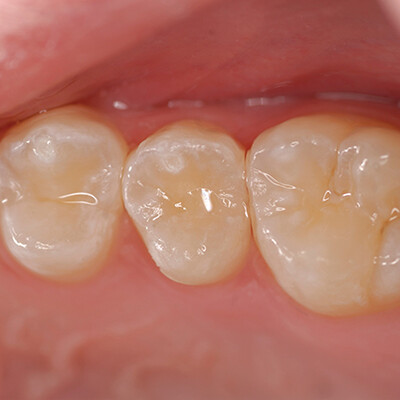

Случай 3: EQUIA Forte HT на зубе № 4 DO

EQUIA Forte HT также является подходящим реставрационным материалом для постоянных зубов. В данном случае зуб № 4 был обработан дистально-окклюзионной (DO) щелевой препаровкой (рис. 7). EQUIA Forte HT Fil был смешан, установлен и контурирован, а EQUIA Forte Coat был нанесен и светоотвержден (рис. 8). Отличное совпадение цвета и способность материала принимать цвет структуры зуба вокруг него были очевидны.